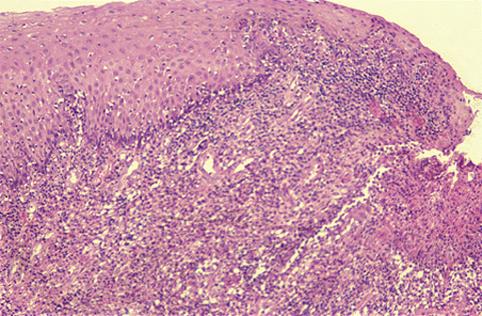

疾患(病理主体)の分類炎症性・潰瘍性疾患/単純性潰瘍

部位(臓器別)食道/下

検査方法ミクロ

病変の最大径(ミリ)20〜24